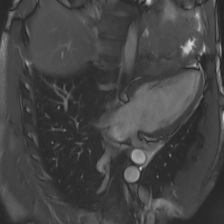

Accurate segmentation and motion estimation of myocardium have always been important in clinic field, which essentially contribute to the downstream diagnosis. However, existing methods cannot always guarantee the shape integrity for myocardium segmentation. In addition, motion estimation requires point correspondence on the myocardium region across different frames. In this paper, we propose a novel end-to-end deep statistic shape model to focus on myocardium segmentation with both shape integrity and boundary correspondence preserving. Specifically, myocardium shapes are represented by a fixed number of points, whose variations are extracted by Principal Component Analysis (PCA). Deep neural network is used to predict the transformation parameters (both affine and deformation), which are then used to warp the mean point cloud to the image domain. Furthermore, a differentiable rendering layer is introduced to incorporate mask supervision into the framework to learn more accurate point clouds. In this way, the proposed method is able to consistently produce anatomically reasonable segmentation mask without post processing. Additionally, the predicted point cloud guarantees boundary correspondence for sequential images, which contributes to the downstream tasks, such as the motion estimation of myocardium. We conduct several experiments to demonstrate the effectiveness of the proposed method on several benchmark datasets.